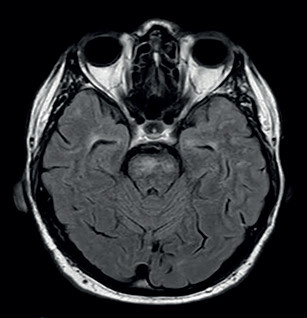

V lednu 2020 byl pacient opět hospitalizován na našem oddělení. V mezidobí mu byla přiznána invalidita I. stupně. Doporučenou ASA a atorvastatin přestal užívat. Byl skeptický a negativistický, měl potíže s krátkodobou pamětí, občas se objevil sklon k emoční labilitě a impulzivitě. Důvodem přijetí k hospitalizaci byla čtyři dny narůstající kmenová symptomatologie pod obrazem dysartrie, parézy n. III vlevo, parézy n. VII vlevo, lehké kvadruparézy a ataxie. Pacient byl orientovaný všemi modalitami, psychomotorické tempo bylo pomalejší. Řeč byla plynulá a srozumitelná. Stoj a chůze byly nestabilní, nebyl schopen samostatné chůze. Vyšetření MR mozku verifikovalo recentní ischemii v pontu velikosti 6 mm, splývající změny bílé hmoty byly v mírné progresi ve srovnání s předchozími vyšetřeními (obr. 3, obr. 4). Podle MRA a neurosonologie byl nález na extra‑ i intrakraniálních tepnách bez významnější patologie. Při biochemickém vyšetření séra byla nově zjištěna hyperhomocysteinemie. Hereditární trombofilie a Fabryho nemoc nebyly prokázány. Do medikace byla vrácena ASA, zvýšena dávka atorvastatinu (80 mg denně) a přidána kyselina listová. Kontrolní náběry na vaskulitidy byly negativní nebo v normě. Při kontrolním vyšetření likvoru byla zjištěna elevace bílkoviny (0,86 g/l), mírná lymfocytární pleocytóza, nespecifické zvýšení koncentrace cytokinů (IL‑1 a IL‑8), C‑reaktivního proteinu (CRP), C3 složky komplementu a vyšší koncentrace neurofilament i proteinu S100, ostatní nálezy byly obdobné jako v dubnu 2019. Při Mini mental testu (MMSE) dosáhl pacient 26 bodů, při Montrealském kognitivním testu (MoCA) činila dosažená hodnota 18. Narušena byla krátkodobá paměť, zrakově‑prostorové a exekutivní funkce. Neurologický deficit byl bez podstatné změny. Pro zvažovanou možnost malotepenné varianty primární angiitidy centrálního nervové systému (PACNS) byl intravenózně podán pulz methylprednisolonu v celkové dávce 3,5 g s následným tapperem per os, ale léčba nepřinesla žádoucí efekt. Pro depresivní ladění pacienta byl k léčbě přidán citalopram v dávce 20 mg denně a na noc mirtazapin v dávce 15 mg. Monitorace EKG a Holterovo monitorování EKG neprokázaly fibrilaci síní nebo jinou srdeční arytmii. Krevní tlak pacienta se pohyboval převážně v hodnotách do 120/80 mm Hg. Transtorakální a transezofageální echokardiografie, stejně jako ultrazvukové vyšetření ledvin a renálních tepen byly normální a odpovídaly věku. Pro upřesnění diagnózy, především směrem k malotepenné variantě PACNS a dědičným nemocem postihujícím bílou hmotu mozku včetně onemocnění CADASIL či CARASIL, byl pacient přeložen na neurologickou kliniku FN v Motole k doplnění digitální subtrakční angiografie (DSA) mozkových tepen, genetického vyšetření a případně i mozkové biopsie. Z provedených vyšetření: oční vyšetření nezjistilo vaskulitidu drobných cév oka, DSA neprokázala vaskulitidu mozkových tepen. Dle neuropsychologického vyšetření byl přítomen selektivní kognitivní deficit na úrovni syndromu mírné kognitivní poruchy (amnestické, vícedoménové a nehipokampální) s dominujícím zpomalením psychomotorického tempa, výrazným narušením pracovní paměti, výbavnosti a exekutivních či zrakově‑prostorových funkcí (především v oblasti konstrukce a ve zrakové diskriminaci komplexních podnětů). V prožívání dominovalo subdepresivní ladění, nestabilní emotivita a pohotovost k pláči. Při molekulárně genetickém vyšetření sekvenováním PCR produktů genu NOCTH3 byla prokázána patogenní heterozygotní mutace c.2989T>C(p.997R). Další léčba probíhala na neurologickém a rehabilitačním oddělení naší nemocnice. Poslední únorový den roku 2020 byl pacient propuštěn do domácí péče. Při propuštění byl schopen samostatné chůze s oporou francouzské hole nebo s rolátorem, modifikovaná Rankinova škála (mRS) = 3, skóre indexu Barthelové = 70, funkční míra nezávislosti (FIM) se pohybovala na hodnotě 5–7 ve většině činností (činnosti vykonával pacient buď sám, s pomůckami nebo pod dozorem druhé osoby). Plánované ambulantní kontroly byly znemožněny nástupem pandemie covidu‑19 a souvisejících epidemiologických opatření. V červnu 2021 absolvoval nemocný kontrolní vyšetření MR mozku se stacionárním nálezem rozsáhlé a splývající gliózy v obou mozkových hemisférách, mezencefalu a pontu. Stejně jako při předchozích vyšetřeních (únor 2019, leden 2020) nebyly postiženy temporální laloky, vnější kapsula byla postižena mírněji než kapsula vnitřní (obr. 5). Pacienta v říjnu 2021 a dubnu 2023 postihly další iCMP z levého karotického povodí, obě iCMP byly úspěšně léčeny intravenózní trombolýzou. V roce 2022 prodělal fokální levostranný motorický epileptický záchvat, pro který byla zahájena léčba valproátem v dávce 2× 500 mg denně. Prohlubuje se kognitivní deficit.